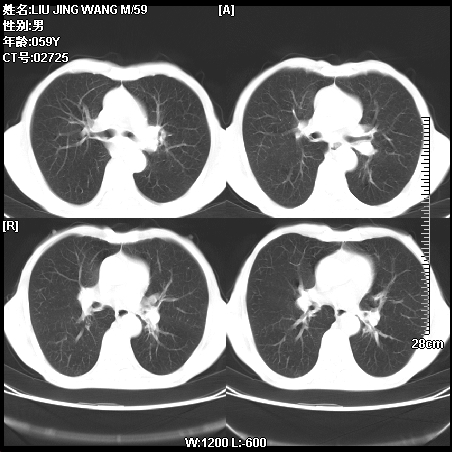

肿瘤科住院病人,都有食管癌史,都有放化疗治疗,两下肺病变是转移灶?还是其他原因造成?请老师指点

病例一 现呼吸困难,经抢救多次,咳嗽咳痰,发现食管癌2个多月

第一个病例我感觉不是转移,第二个是个放射性肺炎;但两个都有纵隔淋巴结肿大,以第二个为主;请楼主参考

符合放射性肺炎,第一例不除外坠积效应